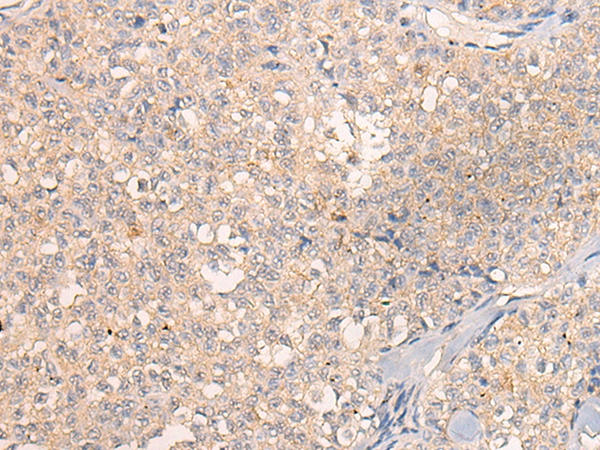

The image on the left is immunohistochemistry of paraffin-embedded Human ovarian cancer tissue using 46498(CHST11 Antibody) at dilution 1/25, on the right is treated with fusion protein. (Original magnification: x200)

The image on the left is immunohistochemistry of paraffin-embedded Human esophagus cancer tissue using 46498(CHST11 Antibody) at dilution 1/25, on the right is treated with fusion protein. (Original magnification: x200)